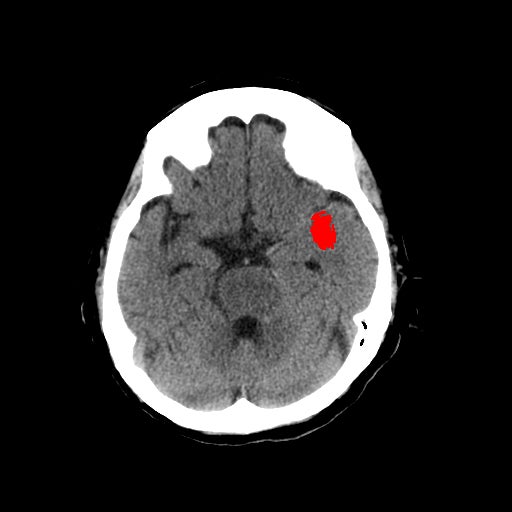

1-1. 高吸収領域の検出・表示例(下)

頭部CT検査において、周囲に比べ白く映る部分(高吸収領域)が見られる場合には、脳出血が疑われます。脳出血は高血圧・脳腫瘍・脳血管の異常などが要因となり、脳の動脈が破れて脳内部に出血した状態を指します。一方、周囲に比べ黒く映る部分(低吸収領域)が見られる場合には、脳梗塞が疑われます。脳梗塞は、脳内の血管が詰まるなどにより血液の流入が止まり、脳に酸素や栄養が行き渡らなくなる状態です。また、急性期の脳梗塞では、頭部CT検査において、灰白質と白質の境界が消失するなどの所見(ECS=early CT sign)が見られ(2)、こうした所見を見落とさずに治療につなげることが肝要です。